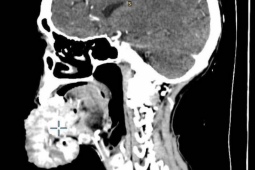

Sở Y tế Quận St. Louis cho biết người đàn ông 54 tuổi đã bị nhiễm vi khuẩn Vibrio vulnificus, một loại vi khuẩn được tìm thấy trong hàu và các loại hải sản khác. Vi khuẩn này thường được tìm thấy trong vùng nước nóng ven biển, nhất vào mùa hè.

Được biết, những người nhiễm Vibrio vulnificus thường bắt đầu có các triệu chứng từ 12 đến 72 giờ sau khi ăn hải sản sống hoặc chín chưa kỹ. Tuy nhiên có thể mất đến 1 tuần trước khi các triệu chứng xuất hiện.

Theo các nhà chức trách y tế, các triệu chứng do vi khuẩn gây ra có thể bao gồm đau bụng, buồn nôn, nôn mửa, sốt. Trường hợp bệnh nặng và tử vong hiếm khi xảy ra nhưng thường xảy ra ở những người có hệ miễn dịch yếu.

Tỷ lệ tử vong do nhiễm Vibrio vulnificus ở Mỹ là khoảng 33%. Theo Sở Y tế quận St. Louis, Vibrio vulnificus gây ra hơn 95% số người tử vong liên quan đến hải sản.